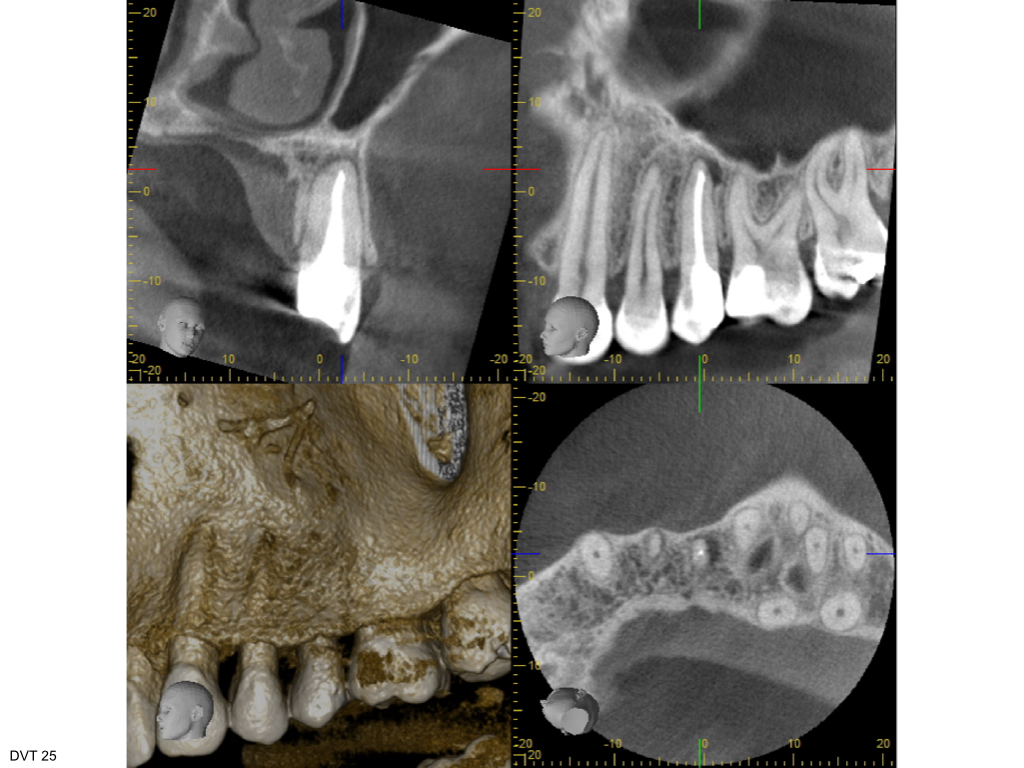

WS11.003 Veröffentlicht 11. November 2014 am 1024 × 768 in Fragestellung: Parodontitis apicalis? (3) Screenshot DVT 25